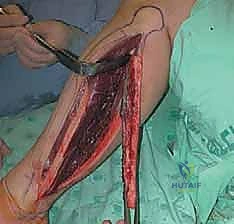

المرحلة الثانية: استئصال الطعم العظمي (Harvesting the Graft)

يقوم الجراح بعمل شق دقيق في الساق لاستخراج الجزء المطلوب من عظمة الشظية. الخطوة الأكثر حساسية هنا هي تسليك الشريان والوريد الشظوي الملتصقين بالعظمة دون إتلافهما، وقطعهما فقط عندما يكون موقع الاستقبال جاهزاً تماماً لتقليل فترة انقطاع الدم (Ischemia time).